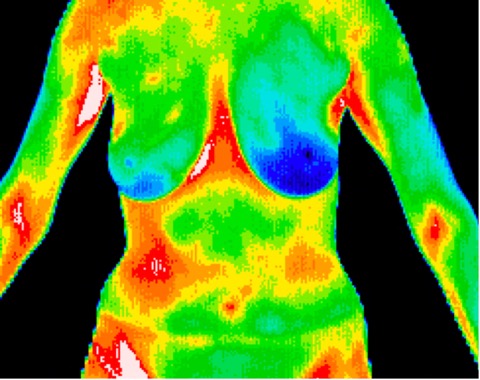

Images of pain syndromes